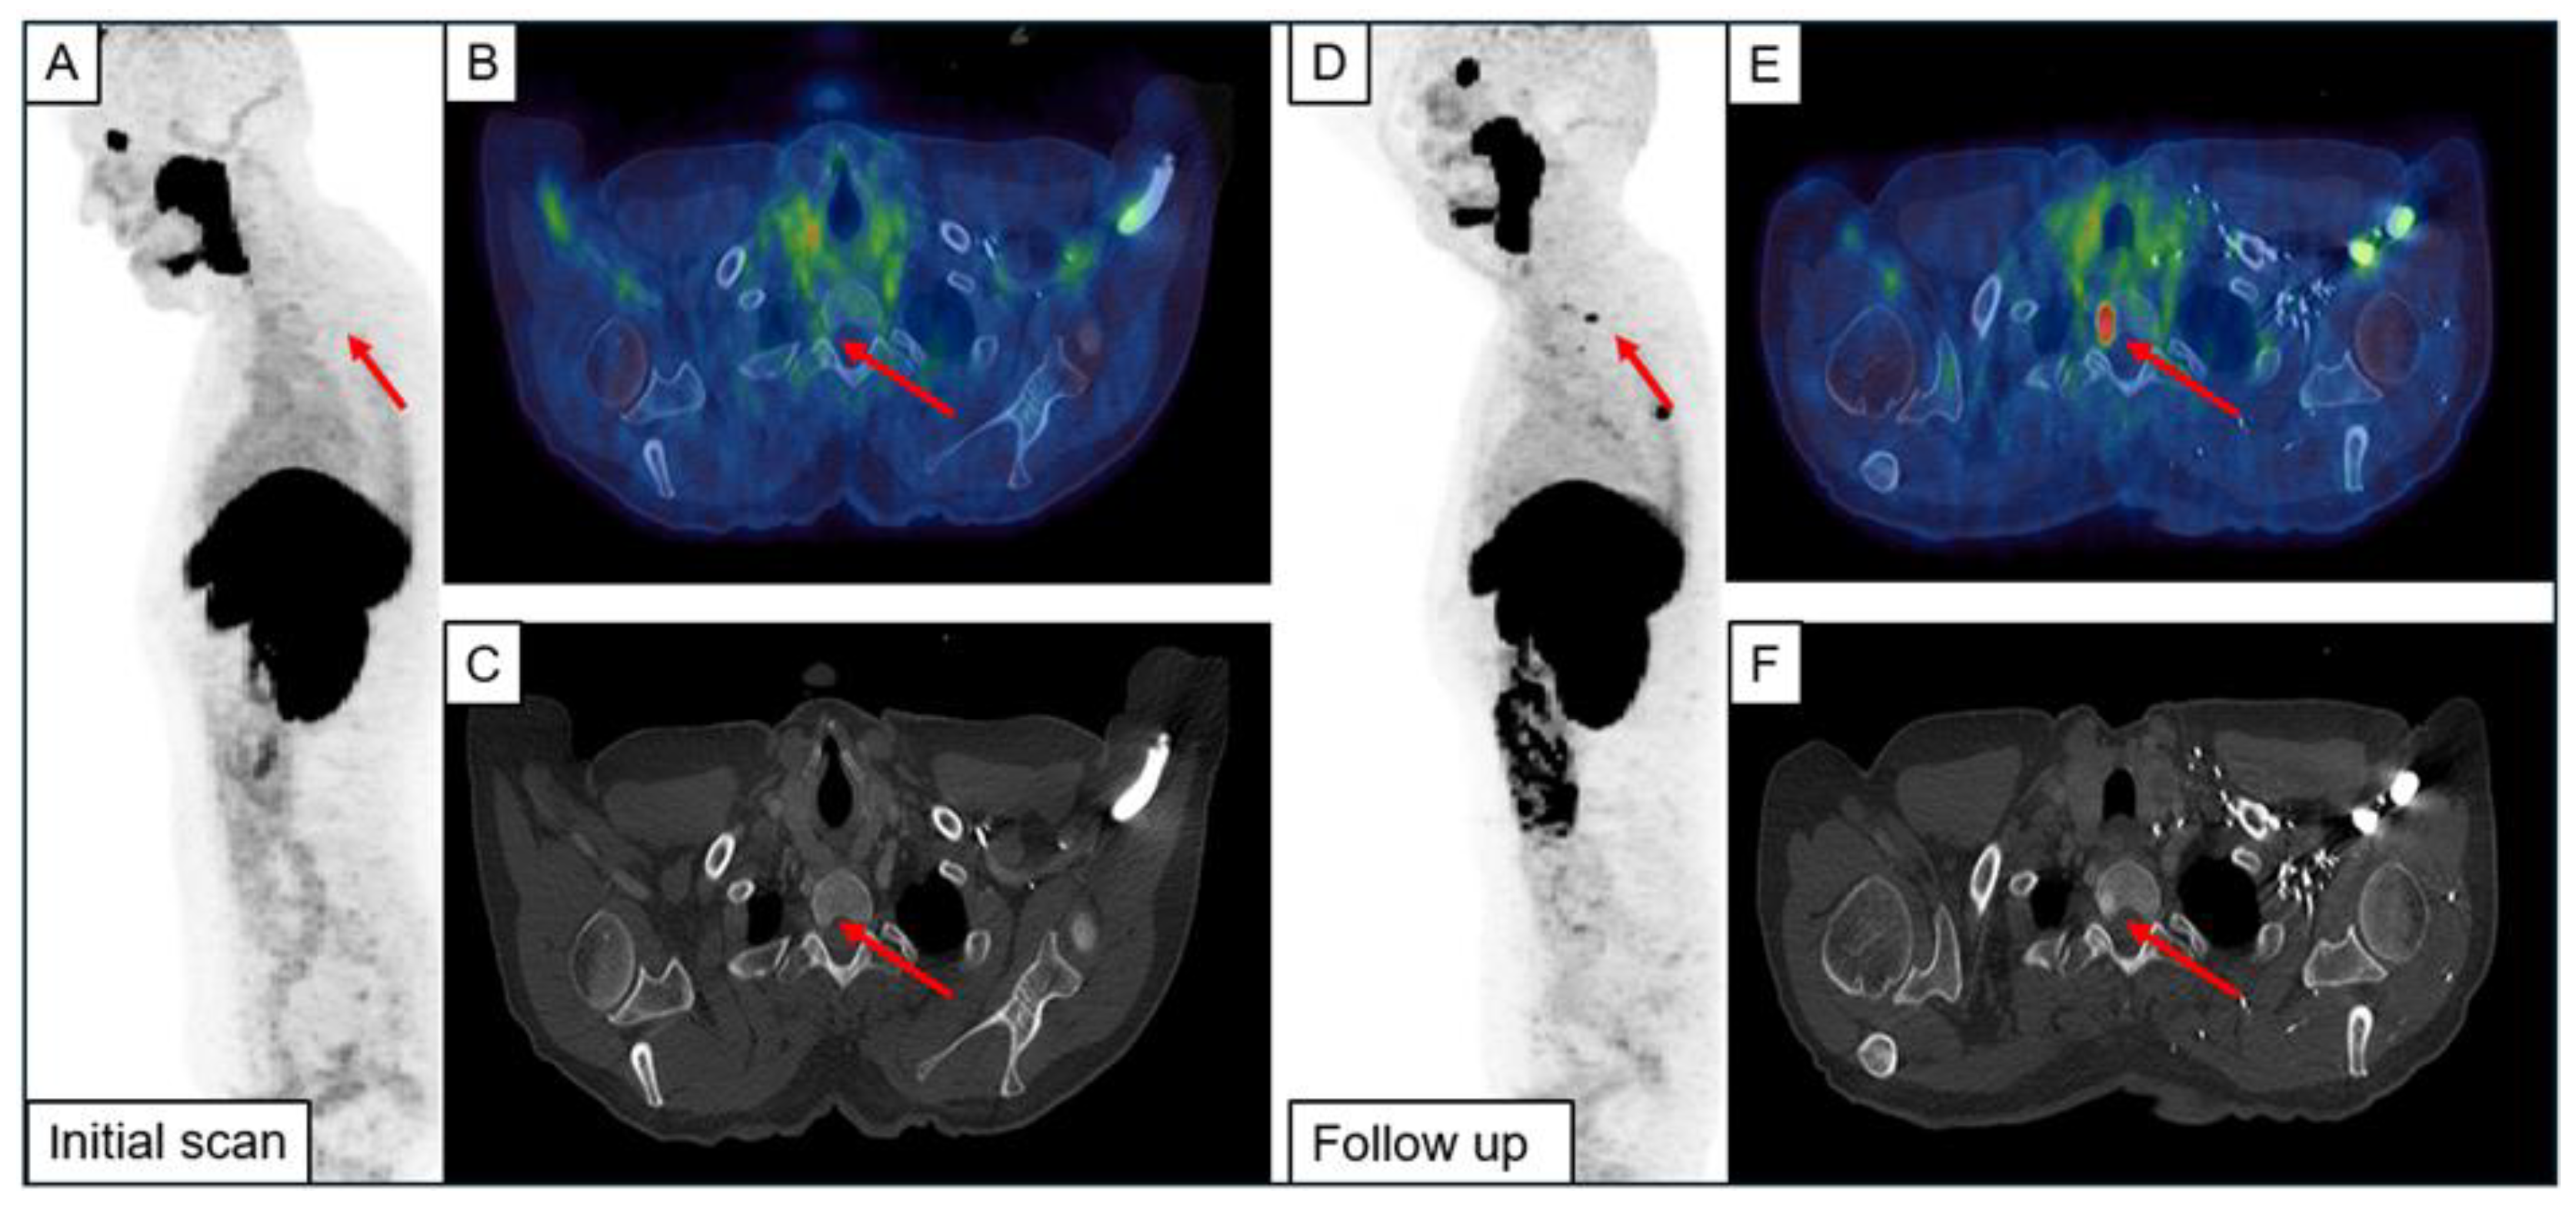

3.2. Follow-Up Examination